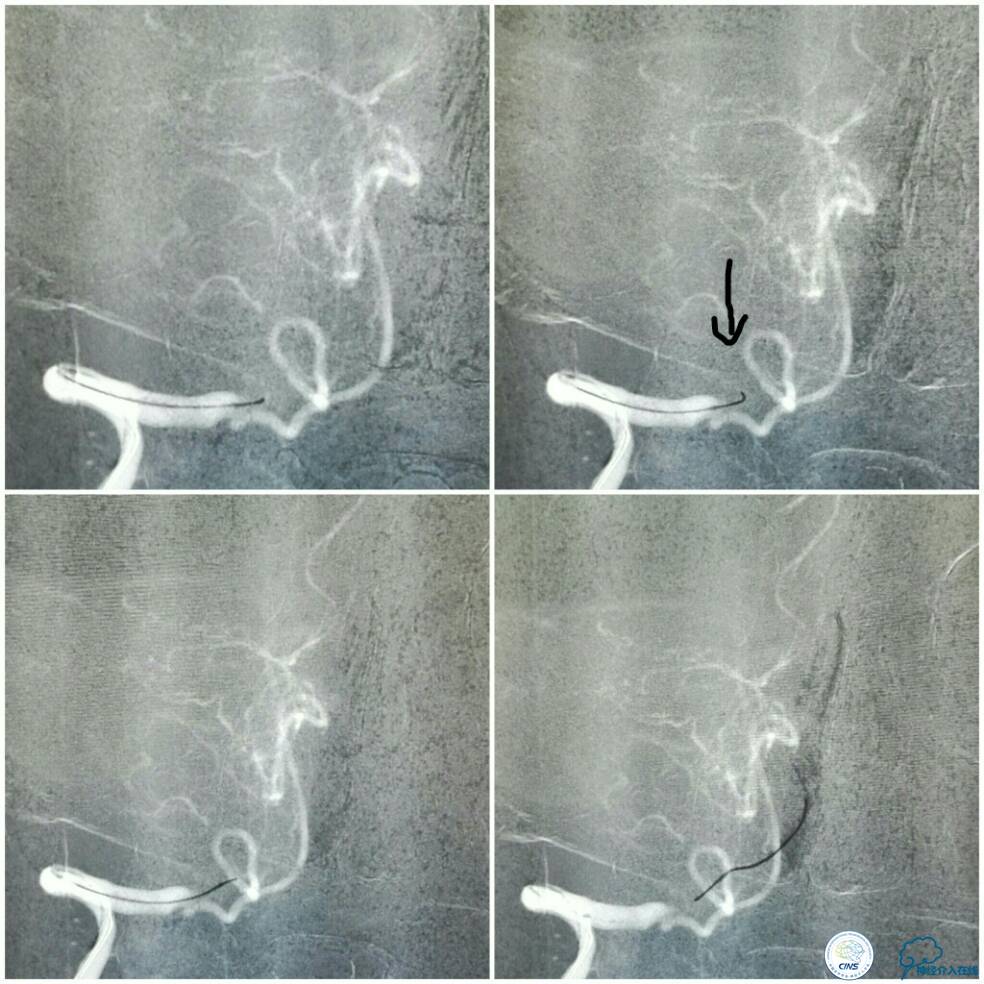

全麻下双股动脉穿刺,分别置入6F及5F动脉鞘。6F导引导管置于右椎动脉V2段,Traxcess 微导丝与Echelon 10微导管同轴,经多次尝试后送达基底动脉(图8);操作过程中见微导丝头端打折变向,此时手控导丝有阻力感,考虑是闭塞病变的近心端(图8箭头),当微导丝越过闭塞段进入血栓,此时微导丝及微管前行无明显阻力。